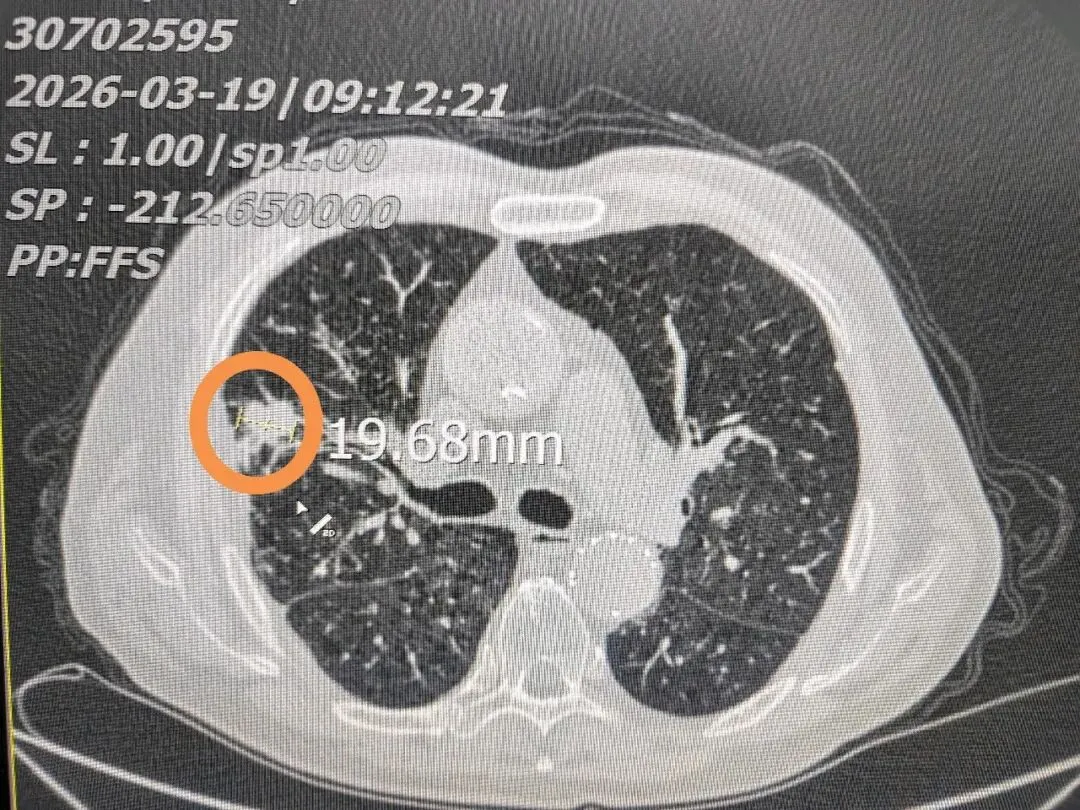

75岁张先生,3年前在当地县医院检查发现右上肺占位性结节,近期复查CT提示结节较前增大,经熟人介绍前来就诊。患者肺部结节直径约1.9cm,体积并不算大,但基础情况十分复杂。

综合评估后,我们为患者选择了肺结节消融治疗。术中将消融针精准穿刺至结节部位,通过针尖产生120~150℃高温,对肿瘤及周边安全范围内组织进行彻底灭活,术后患者恢复顺利。